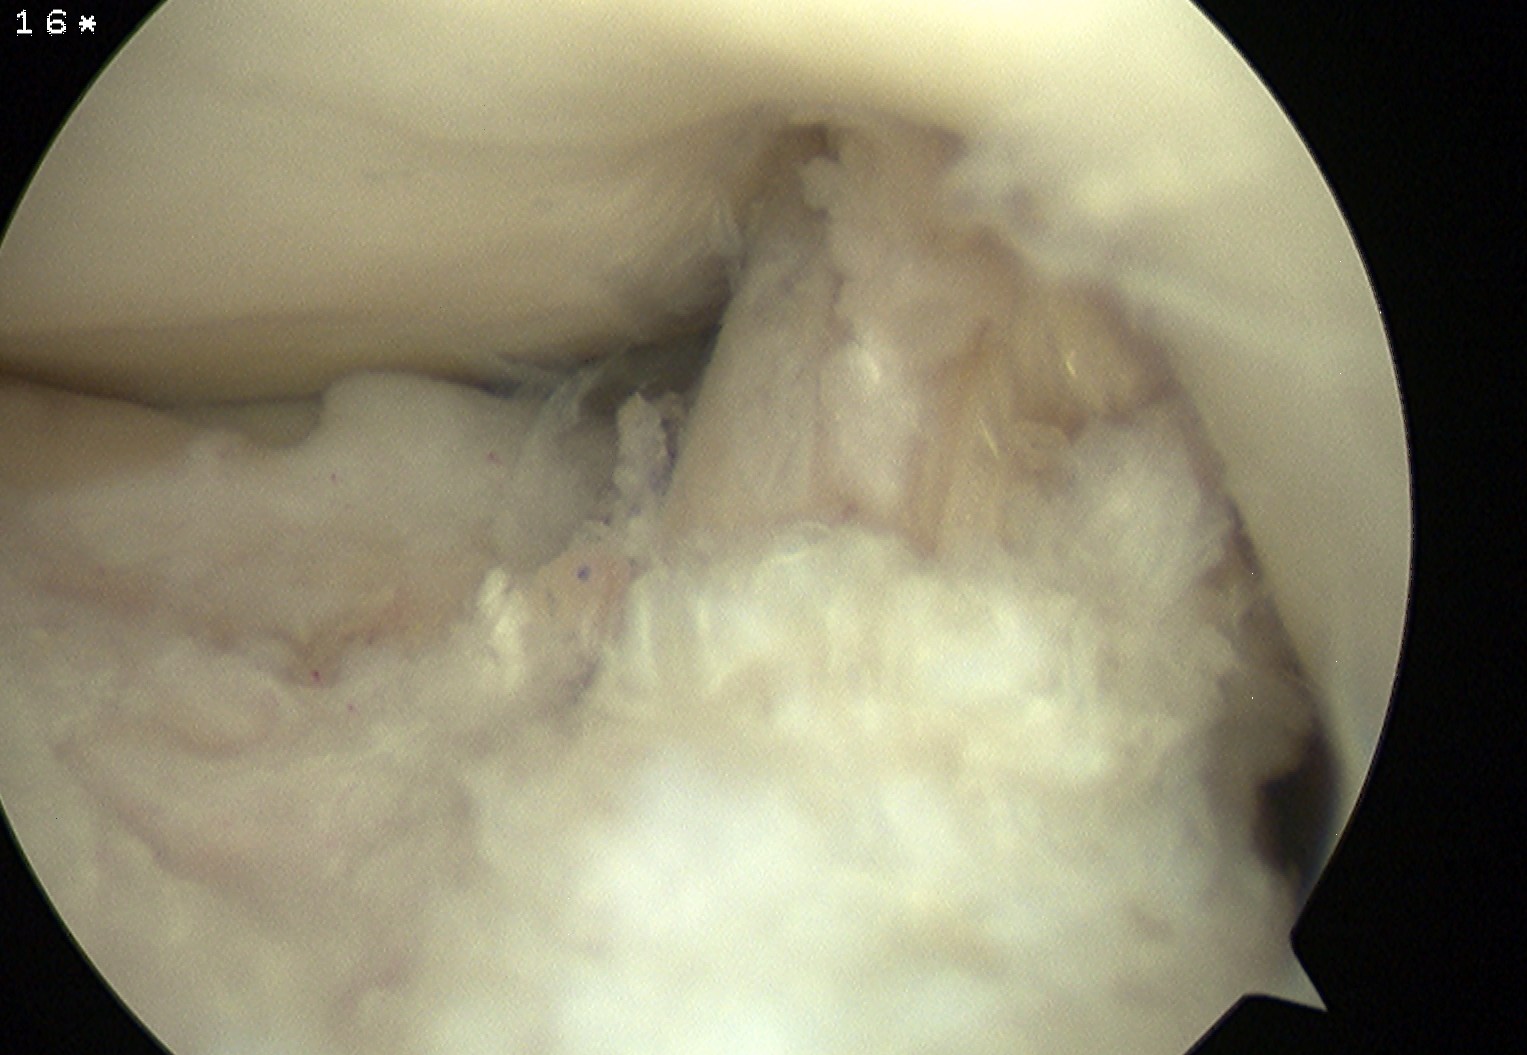

Range

Ensure no anterior or lateral impingement of graft

- can perform careful notchplasty